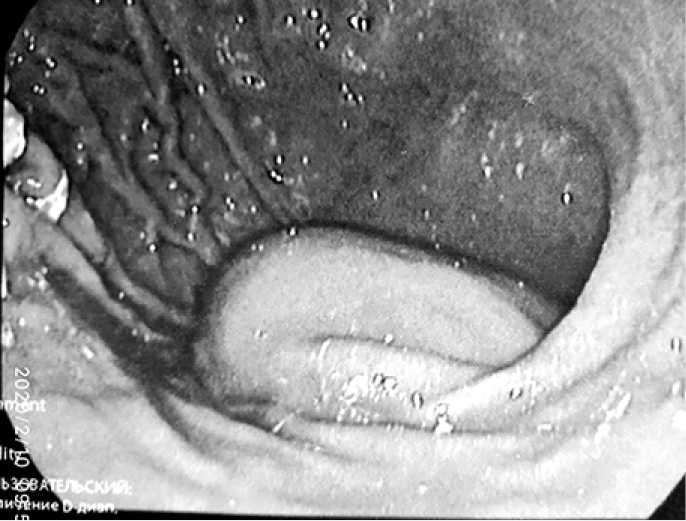

С диагнозом: «Tumor брюшной полости» поступил 02.07.2019 г. в хирургическое отделение КГБУЗ «Городская больница № 5 г. Барнаула», где провели уточняющую диагностику – эндоультрасонография от 03.07.2019 г. Видеогастроскоп проведён в желудок. Стенки желудка хорошо расправляются воздухом. В просвете желудка на большой кривизне дистальной части тела желудка на 2/3 шаровидное эластичное выбухание с подвижной гиперемированной слизистой оболочкой диаметром до 70 мм (рис. 5–7), эндосонограф свободно проведён. Сканирование в режиме 7,5–10,0 МГц. Полостное жидкостное образование диаметром 63 мм, пристеночно содержит гипоэхогенную ткань толщиной местами до 15 мм. Капсула гиперэхогенная до 1,4 мм. ЦДК (-). Образование расположено в подслизистом слое. Чётко прослеживается мышечный слой за её пределами (рис. 8, 9). Между желудком и печенью гипоэхогенная ткань с наличием сосудов и анэхогенной полостью до 10 мм (рис. 10).

Рис. 8. Образование расположено в подслизистом слое. Чётко прослеживается мышечный слой за её пределами

Рис. 9. Образование расположено в подслизистом слое. Чётко прослеживается мышечный слой за её пределами